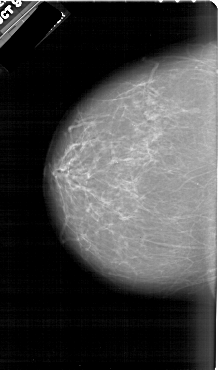

A_1950_1.LEFT_MLO

LEFT_CC LINES 6646 PIXELS_PER_LINE 3931 BITS_PER_PIXEL 12 RESOLUTION 43.5 NON_OVERLAY